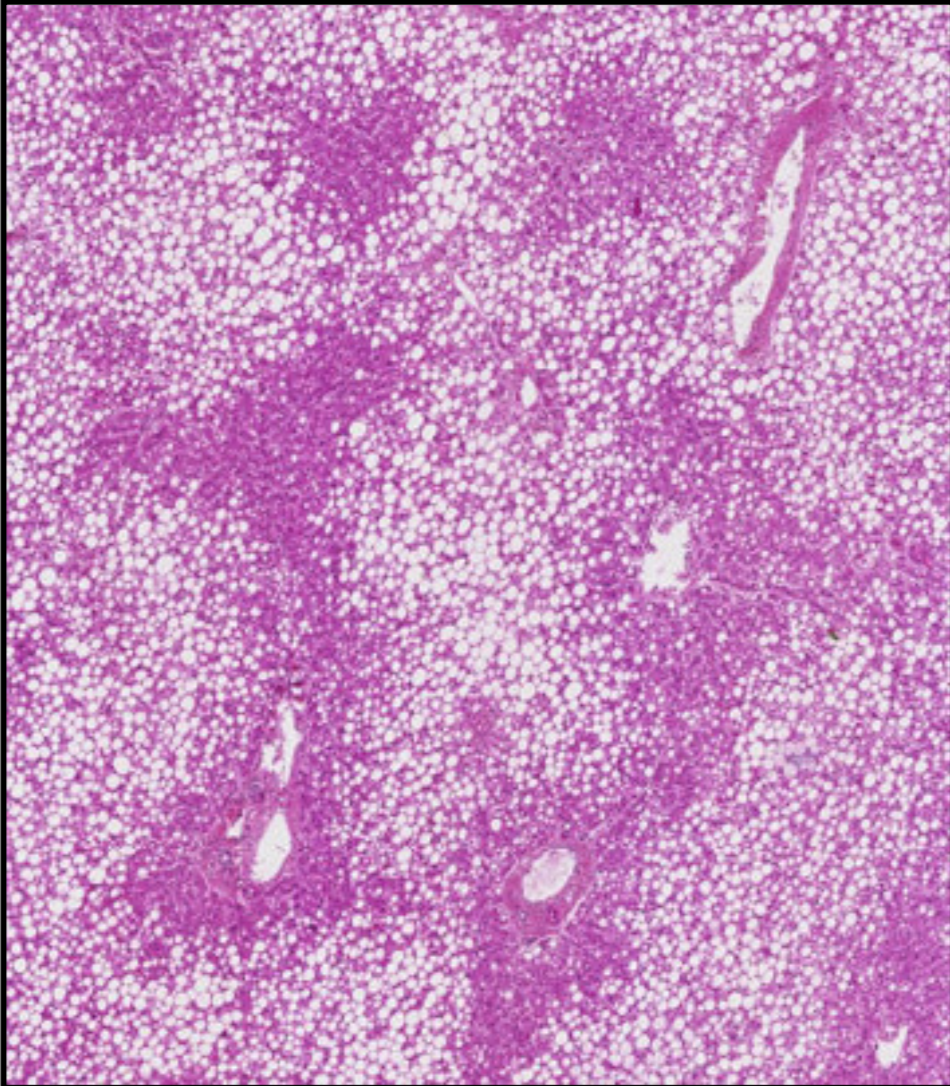

stéatose du foie